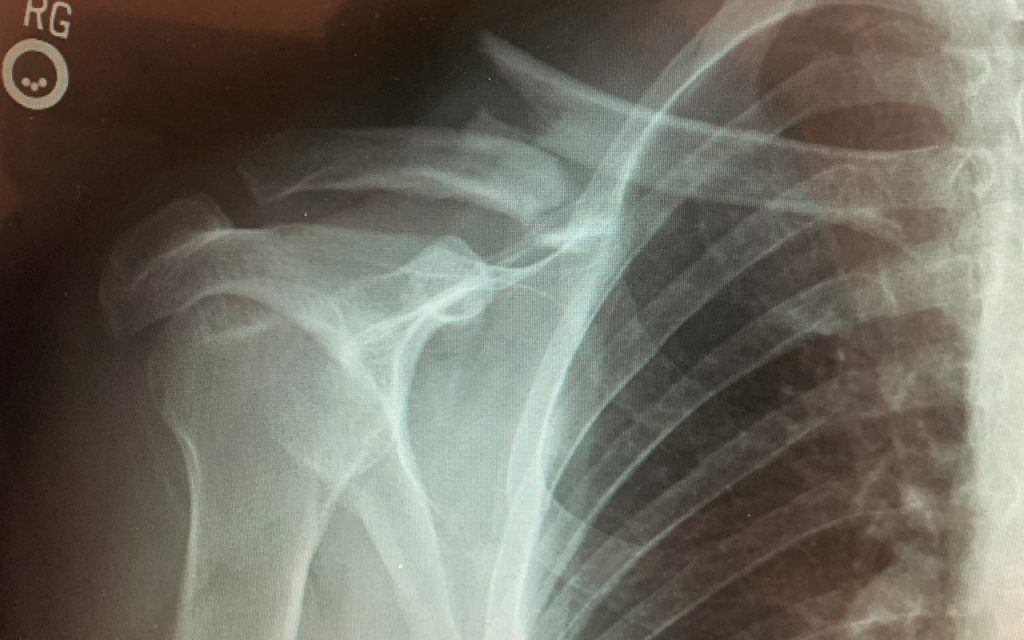

Dr. David Kornreich, one of the excellent surgeons at the Orthopaedic Hospital of Wisconsin, recently experienced a clavicle fracture requiring